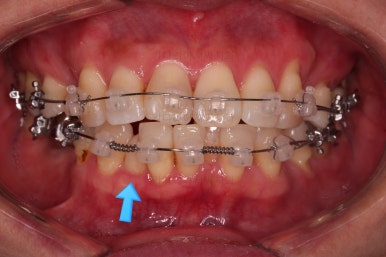

비밀은 바로 화살표에 있습니다.

유치 잔존

말그대로 어릴 때 빠져야 할 유치가 남아있다는 뜻인데요.

앞니 사이에 뾰족하게 남아있다 보니 자리만 많이 차지하고 있는 모습이었고 다른 영구치를 더 삐뚤게 만들었어요.

장치를 부착했습니다.

이번 환자분이 선택한 장치는 데이몬 클리어라고 하는 현존하는 자가결찰 세라믹 장치 중에 가장 심미적인 장치입니다.

사실상 멀리서 보면 철사를 제외하고는 거의 눈에 띄지 않는 모습인데요.

단점은 부피가 다른 장치들보다 약간은 더 크기 때문에 입이 약간 더 나와보일 수 있다는 점이죠.

아직 아래 앞니에 있는 유치는 발치하지 않았는데요.

현 상태로 발치를 하게 되면 기구 접근이 되지 않아 광범위하게 뼈를 갈아내며 뽑아야 됩니다.

교정을 하면 기구 접근이 충분히 되도록 공간을 벌린 뒤 발치를 할 수 있어 기간은 더 걸릴 수 있겠지만 잇몸뼈를 보존하고 수월하게 발치를 하려면 교정만한게 또 없죠.